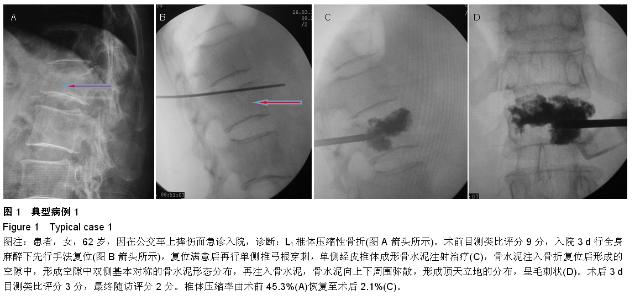

METHODS: A total of 53 patients with single vertebral osteoporotic vertebral compression fractures, who were treated with percutaneous vertebroplasty, were retrospectively analyzed from July 2012 to December 2014. The new method group (32 cases) received manual reduction, underwent unilateral pedicle puncture and bone

cement injection during unilateral percutaneous vertebroplasty under general anesthesia. The conventional method group (21 cases) received conventional percutaneous vertebroplasty.

RESULTS AND CONCLUSION: There was an average of 6-month follow-up (3-14 months). Significant differences in visual analogue scale scores, vertebral compression ratio and kyphosis Cobb’s angle were detected in the new method and the conventional method groups at 3 days post surgery and during final follow-up compared with before surgery (P < 0.01). No significant difference in visual analogue scale scores was found between the two groups (P > 0.05). Compared with the conventional method group, postoperative vertebral compression ratio, kyphosis Cobb’s angle and bone cement leakage rate were significantly lower in the new method group (P < 0.01). Results verified that the new method combined with the advantages of percutaneous vertebroplasty and percutaneous kyphoplasty, the advantages of unilateral and bilateral puncture approach. The new method can correct kyphosis deformity, effectively recover the vertebral height and physiological curvature and the puncture is safe. Simultaneously, the leakage rate of bone cement is reduced, and the distribution of bone cement is ideal.